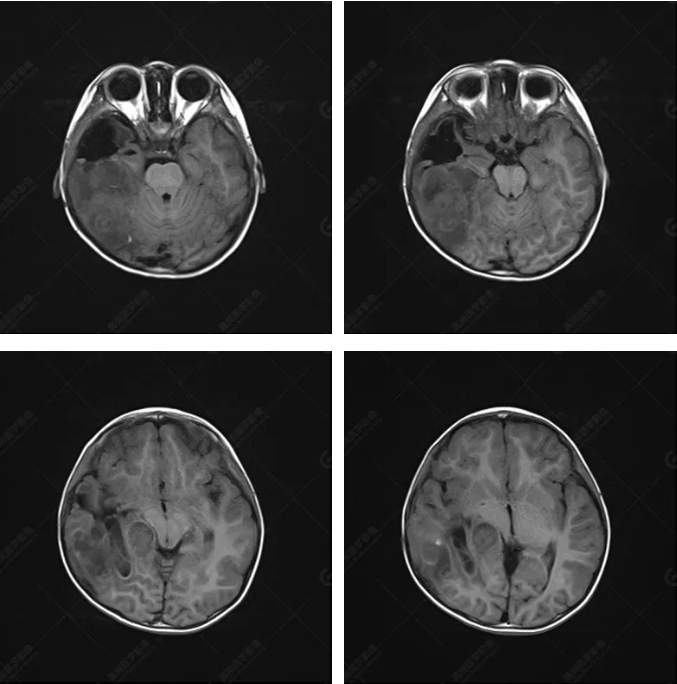

右側(cè)顳葉腫瘤切除術(shù)后(具體不詳):右側(cè)顳部骨質(zhì)不連續(xù)呈術(shù)后改變,右側(cè)顳葉術(shù)區(qū)見(jiàn)片狀長(zhǎng)T1長(zhǎng)T2信號(hào)影,F(xiàn)LAIR呈低信號(hào);術(shù)區(qū)后方右側(cè)顳枕葉見(jiàn)一巨大占位性病變影,邊界欠清,大小約6.2×5.8×4.3cm(前后×左右×上下),信號(hào)不均勻,T1WI呈等稍低信號(hào)間雜少許高信號(hào),T2WI呈高稍低混雜信號(hào),DWI示部分病灶彌散受限,相應(yīng)ADC圖減低,磁敏感序列見(jiàn)部分呈極低信號(hào),增強(qiáng)掃描可見(jiàn)明顯不均勻強(qiáng)化,鄰近硬腦膜及小腦幕增厚并明顯強(qiáng)化;另延髓右前方及右側(cè)橋小腦角區(qū)見(jiàn)一不規(guī)則形異常信號(hào)影,大小約3.2×1.3×3.7cm(左右×前后×上下),呈長(zhǎng)T1稍長(zhǎng)T2信號(hào),F(xiàn)LAIR呈等信號(hào),DWI未見(jiàn)受限,增強(qiáng)后明顯均勻強(qiáng)化,鄰近腦膜明顯強(qiáng)化。鄰近腦實(shí)質(zhì)及右側(cè)顳角明顯受壓;左側(cè)大腦半球未見(jiàn)局灶性信號(hào)異常,中線結(jié)構(gòu)稍左移。

右側(cè)顳葉腫瘤切除術(shù)后:現(xiàn)術(shù)區(qū)后方右側(cè)顳枕葉及延髓右前方占位,右側(cè)顳枕部硬腦膜及小腦幕明顯強(qiáng)化,結(jié)合既往影像資料,考慮為胚胎源性惡性腫瘤,如非典型畸胎樣/橫紋肌樣瘤(AT/RT)或原始神經(jīng)外胚層腫瘤(PNET)。

術(shù)后隨訪病理結(jié)果:非典型畸胎樣/橫紋肌樣瘤。